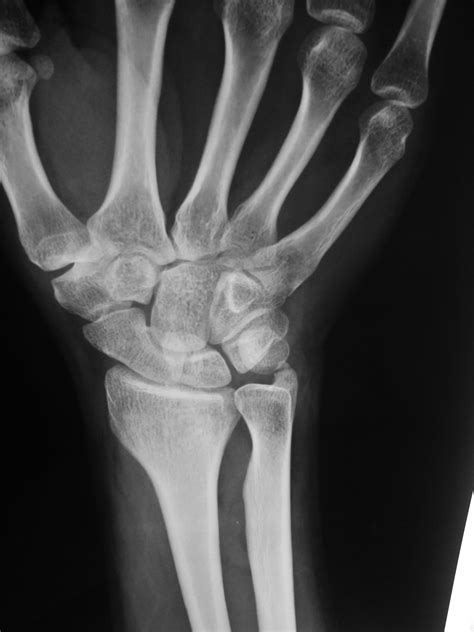

Diagnosing an Ulnar Styloid Fracture

Diagnosing an ulnar styloid fracture typically involves a combination of physical examination and imaging tests. The diagnostic process may include:

• Physical Examination: A healthcare provider will assess the wrist for pain, swelling, and deformity. They may also check the range of motion and stability of the wrist.

• X-rays: These are the primary imaging tool used to confirm the diagnosis. X-rays can show the location and extent of the fracture.